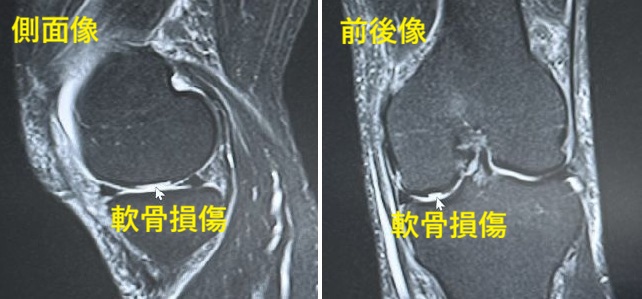

| 変形性関節症とは関節軟骨の老化や磨耗によって起こる軟骨と骨の進行性の変性疾患(加齢的変化)です。体重がかかる荷重関節(膝関節、股関節、足関節、脊椎)は体重がかからない非荷重関節(肩関節、肘関節、手関節)に比べ、変形性関節症の発生を多く認めます。 関節軟骨は骨と骨が接する部分にある軟骨で、関節の動きを滑らかにし衝撃を吸収する役割があります。軟骨は軟骨細胞と軟骨基質(水分+プロテオグリカン+U型コラーゲンなど)より構成されています。 軟骨には血管・神経・リンパ管はありません。したがって軟骨の栄養源は血管からではなく、関節の袋の滑膜から分泌される関節液です。関節液にはヒアルロン酸やタンパク質などの栄養素をたくさん含んでいます。 ヒアルロン酸は潤滑作用を有し摩擦を軽減させ軟骨細胞の形成や修復を促しています。関節液は適度な圧迫(歩行や運動など)により、軟骨の中に浸潤して行きます。 人は加齢とともに骨はもろくなり、筋肉は弱くなり、靭帯は緩んでいきます。軟骨が摩耗すると関節液からの栄養が途絶えて変性(老化)がはじまります。やがて骨も変形し変形性関節症になります。 変形性膝関節症 膝は最も負担がかかる関節です。歩行時は体重の2〜3倍、階段を降りる時は体重の8〜10倍膝に負担がかかると言われております。そのため、膝は容易に変形性関節症を発症します。明らかな原因がない一次性と、明らかに原因のある二次性に分かれます。大半は一次性です。 ■一次性は加齢(老化)を基盤として肥満や機械的刺激、環境因子、遺伝的因子など色々な要因が加わって発症すると考えられています。多くは中高年の女性で年齢と共に進行して行きます。 ■二次性は関節内に原因があって発生するもの(半月板損傷や十字靭帯損傷、側副靭帯損傷、関節内骨折など)と、関節外に原因があって発生するもの(大腿骨近位部骨折や大腿骨骨折、下腿骨骨折など)があります。 症状 変形性膝関節症の経過は車の故障に似ています。エンジンオイルの汚れやブレーキパットの磨耗、タイヤの磨耗などです。新車はトラブルなく快適に走っていますが、中古車になるとエンジンやタイヤは摩耗し、外装は錆び、ひび割れて、やがて廃車になる過程に似ています。 早期の症状は膝の痛みです。大半が膝の内側の痛みです。やがて歩行時痛や階段を降りる時に痛みを訴えます。また膝の腫れ(関節水腫)を認めます。さらに運動障害を認め正座が出来なくなったり、膝が伸びなくなったりします。進行すると不安定感を訴え、歩行が困難となります。 これらの変化は肥満や下肢の筋力低下によって加速度的に進行し、将来、ロコモティブシンドロームへと進展し、やがて介護が必要となります。 診断 診断はレントゲン検査です。所見として関節裂隙の狭小化(軟骨が磨り減り、関節のすき間が狭くなる)や骨棘形成(骨のとげ)、硬化像(骨が変に硬くなる)などを認めます。 大半はO脚です。膝の内側の骨軟骨が壊れ、進行すると外側の骨軟骨や膝蓋骨(お皿)も破綻していきます。時にX脚を認めることもあります。MRIでは骨や軟骨、半月板の詳細な情報をよく観察できます。 治療 1)リハビリテーション リハビリテーションは変形性膝関節症の治療と予防を兼ねています。疼痛緩和に物理療法を行い、膝のストレッチングや股のストレッチング、膝の筋力強化訓練、股の筋力強化訓練などの運動器リハビリテーションを開始します。 膝を鉄筋コンクリートに例えると、骨や軟骨は鉄筋です。筋肉はコンクリートです。骨や軟骨に負担をかけないためには筋肉を強化する運動療法が大切です。さらに大切なことは肥満の解消です。歩行時は体重の2〜3倍、階段を降りる時は8〜10倍膝に負担がかかります。 2)装具療法 内反膝(O脚)のある方は治療目的や進行予防を兼ねて、外側楔状足底板(痛みのある内側の関節軟骨に出来る限り体重がかからないようにするための中敷き)の着用をすすめます。 大半の症例では半月板損傷を合併していますので半月板の逸脱(ずれ)を予防するためにも使用をすすめます。なお高度の変形があり手術(人工関節)を拒まれる方には装着式装具をすすめることもあります。 3)注射療法 注射療法はヒアルロン酸注射とステロイド注射に分かれます。 ■ヒアルロン酸注射は関節軟骨の保護や関節の動きの改善、関節水腫(水がたまる状態)の改善、疼痛緩和の目的で使用されます(車に例えるとエンジンオイルの交換です)。 ■ステロイド関節内注射は炎症が強いときに一次的な疼痛緩和として使用されます。頻回に使用すると骨や軟骨に悪影響を生じますので極力使用を控えます。 4)薬物療法 疼痛緩和にアセトアミノフェン、炎症緩和に非ステロイド系抗炎症剤、外皮用薬などを処方します。効果がなければトラマドール塩酸塩、デュロキセチンなどを検討します。 5)手術的療法 手術的療法には、高位脛骨骨切り術や人工関節単顆置換術、人工関節全置換術などがあります。 ■高位脛骨骨切り術は内反膝(O脚)の症例に行われます。内側の関節軟骨が傷めば、正常な外側の関節軟骨で体重を支えようという発想です。O脚を多少X脚に矯正する手術です。ただし、体格指数・肥満度(BMI)35以上の高度肥満者の長期成績はよくありません。 ■人工関節単顆置換術は人工関節を片側のみ行う人工関節です。外側の関節軟骨が正常で、内側の関節軟骨のみが傷んでいる症例に行われます。 ■人工関節全置換術は内外側ともに傷んでいる症例に行われます(車に例えるとエンジン交換や左右のタイヤ交換です)。しかし人工関節には耐用年数があります。年齢や職業、趣味、基礎疾患、環境因子、体格指数を考慮して検討されます。 なお最近では、関節軟骨損傷や半月板損傷に再生医療の研究が盛んに行われております。将来、期待が持てる分野と思われます。